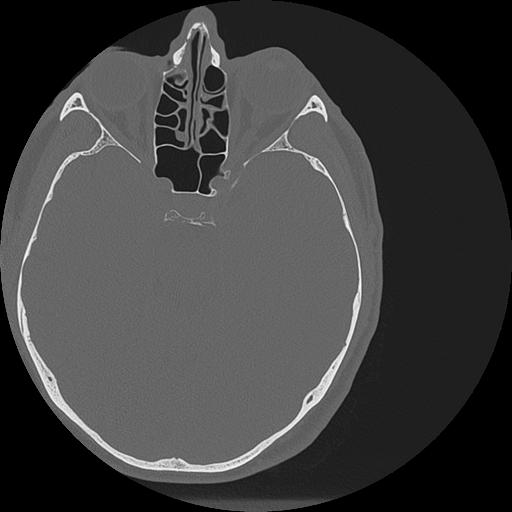

7 HUESO,,Vol,0.5,HUESO,,